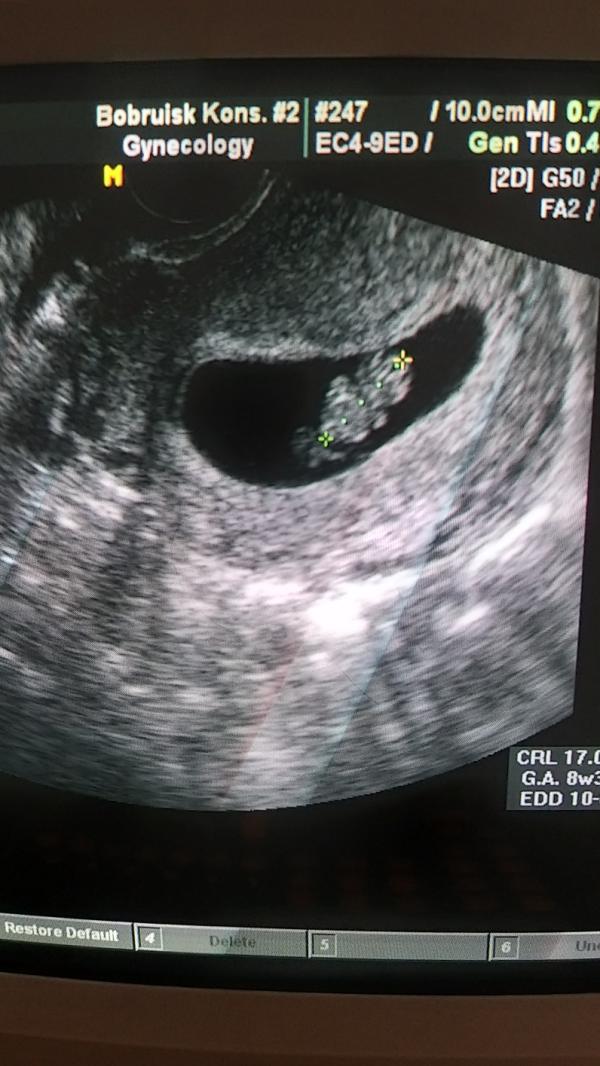

В октябре мы с мужем наконец-то узнали, что я беременна🤩 это было неописуемое словами счастье😋 я сделала тест, он был положительный... поэтому хотелось побыстрее сходить на узи и подтвердить мое положение😊 НО это время немного затянулось, т.к. я заболела.......